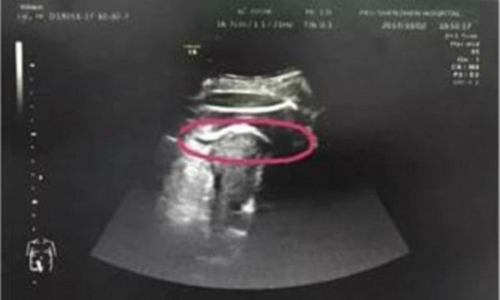

Thai nhi làm thủng tử cung người mẹ